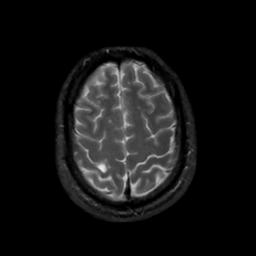

MR Study #10, April 28, 1991 -- Slice #41